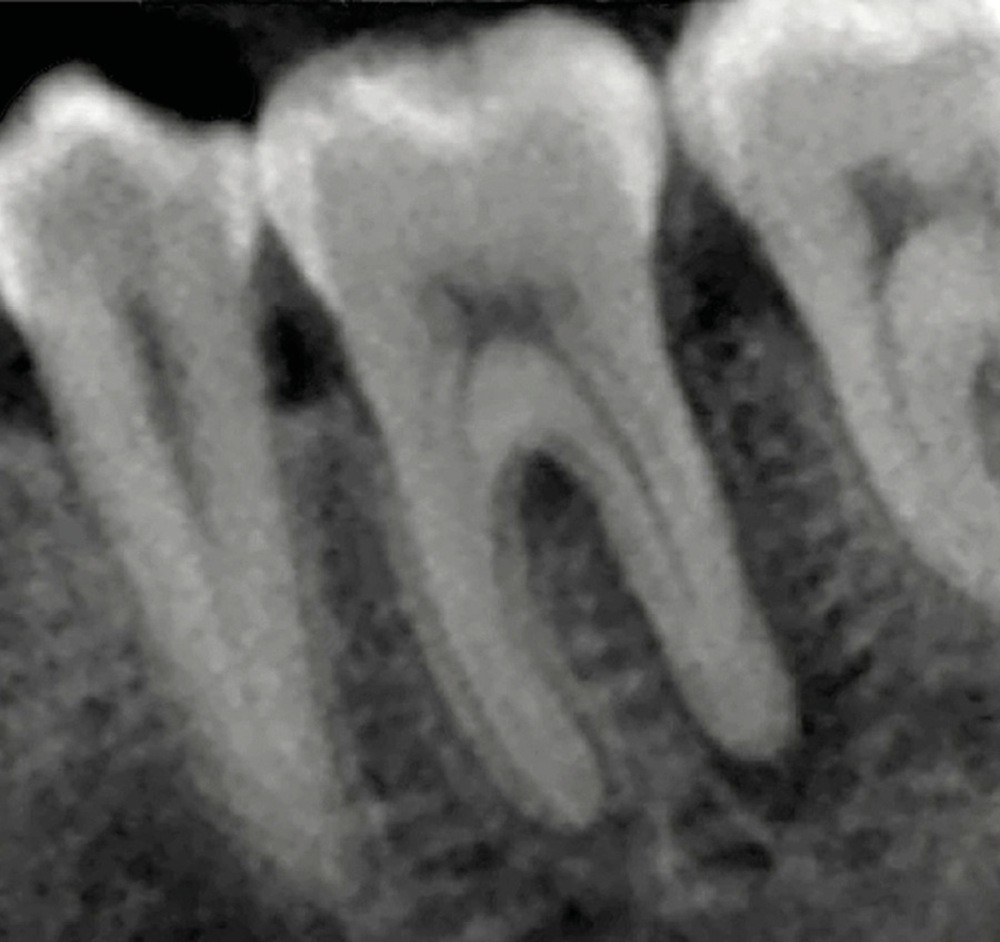

La compréhension de ces instruments, des biomatériaux et des différentes techniques est essentielle, et doit nous guider dans nos prises de décision en fonction des situations cliniques. Dans le cas clinique présent, suivi sur 24 mois, le patient se présente avec des douleurs à la mastication sur la dent 36. Tous les signes cliniques (test au froid négatif, test à la percussion positif, sondage parodontal positif en vestibulo-distal avec présence de fistule) et les examens radiologiques (LIPOE sur la racine distale, lésion inter-radiculaire) convergent vers un diagnostic de nécrose pulpaire due à une fracture longitudinale non complète (type 3 : Classification AAD) [1] (fig. 1).

La mise en forme doit également s’adapter aux singularités anatomiques. Pour ce cas clinique, le canal mésio-lingual a été mis en forme en premier jusqu’à la longueur de travail. Puis le test du cône a été réalisé (fig. 4 et 5) afin de voir si les deux canaux se rejoignaient. Ces deux canaux se rejoignant à 3 mm de l’apex, le canal mésio-vestibulaire a été mis en forme à sa longueur de travail moins 3 mm afin d’éviter la zone de confluence et le risque accru de fracturer un instrument. De plus, cette mise en forme longueur de travail-3 mm a son importance pour la précision de l’obturation et l’ajustage des cônes. Pour le canal distal, qui était un canal « en 8 », nous appliquons le même raisonnement que pour les canaux mésiaux, avec un canal principal, test du cône, et ajustage des maîtres-cônes (fig. 6).